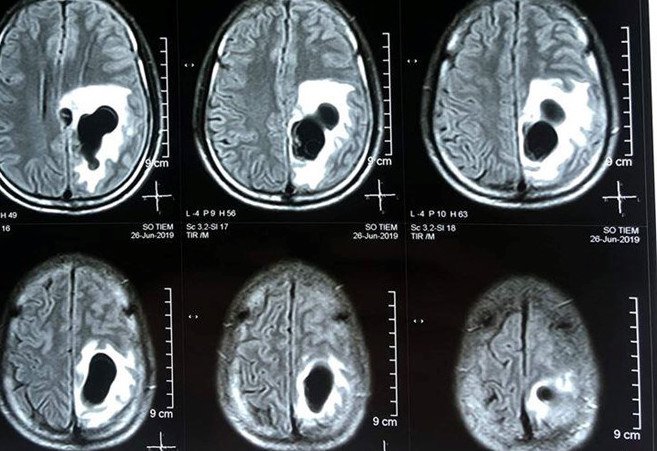

MRI não sử dụng tần số vô tuyến, từ trường và máy tính để tạo ra hình ảnh đặc biệt của não và thân não. Việc khám này còn được gọi là MRI đầu hoặc MRI sọ não. MRI não thường được sử dụng để chẩn đoán đột quỵ, khối u, chứng phình động mạch, xuất huyết, hoặc các bệnh mãn tính khác của hệ thần kinh như bệnh đa xơ cứng. Ngoài ra, nó giúp bác sĩ điều tra các triệu chứng như mờ mắt, chóng mặt, co giật và đau đầu mãn tính. MRI sọ não có thể hữu ích khi kiểm tra tuyến yên hoặc thân não vì các kỹ thuật thông thường như chụp X-quang hoặc CT cung cấp ít chi tiết hơn cho những khu vực này. Trong quá trình chụp ảnh não, bạn sẽ được di chuyển vào đầu máy MRI trước tiên, trên lưng của bạn. Một thiết bị sẽ được đặt xung quanh đầu bạn để giúp chúng tôi có được những hình ảnh tốt nhất có thể về não của bạn.

MRI sọ não giúp chẩn đoán nhanh chóng, phát hiện chính xác các bất thường tại não.

MRI sọ não giúp chẩn đoán nhanh chóng, phát hiện chính xác các bất thường tại não.